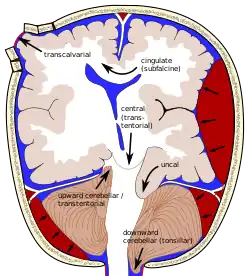

The most common presentation of cerebrovascular diseases is an acute stroke, which occurs when blood supply to the brain is compromised.[13] Symptoms of stroke are usually rapid in onset, and may include weakness of one side of the face or body, numbness on one side of the face or body, inability to produce or understand speech, vision changes, and balance difficulties.[1] Hemorrhagic strokes can present with a very severe, sudden headache associated with vomiting, neck stiffness, and decreased consciousness.[13] Symptoms vary depending on the location and the size of the area of involvement of the stroke. Edema, or swelling, of the brain may occur which increases intracranial pressure and may result in brain herniation. A stroke may result in coma or death if it involves key areas of the brain.[14]